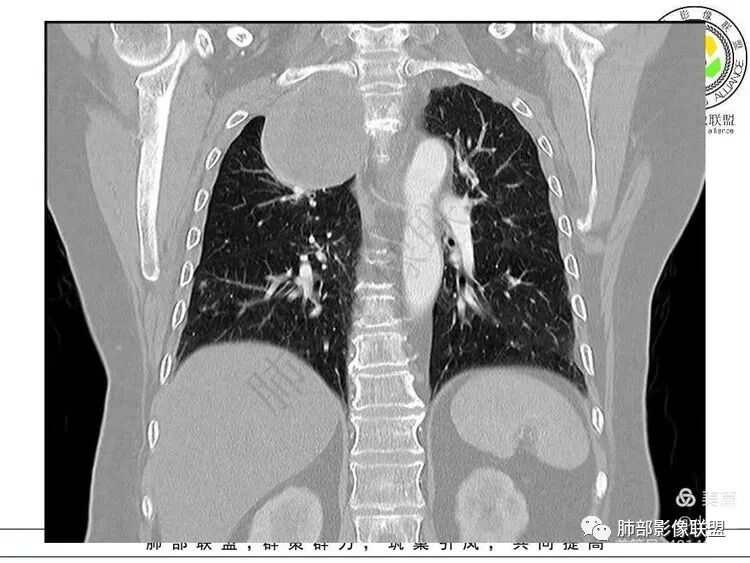

1. 右上胸廓入口区类椭圆形块影,边界清楚光整,纵向“嵌顿”于颈根部及上纵隔,向上推移右锁骨下动静脉,向外下方推移上肺胸膜及肺组织(肺血管、支气管),向前推移上腔静脉,界限清楚。

2. 块影不均匀轻度强化,可见较均匀实性区及液性密度区,未见积气、囊壁样结构、钙化或脂肪密度。可疑部分肋间动脉分支进入。

3.块影相邻椎骨及肋骨明确推压或骨质吸收破坏,未见椎管内结节或椎间孔扩大。

4.双肺门及纵隔未见肿大淋巴结。